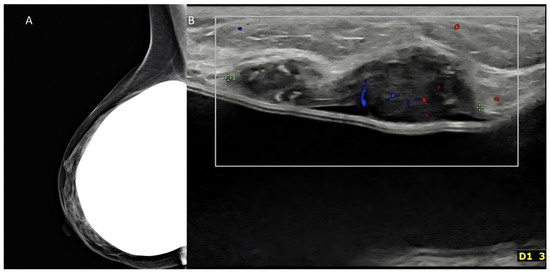

Extended FOV scans allow to display and measure large breast lesions. Additionally, it becomes possible to show the spatial relationship and the distance between a lesion and some anatomic landmarks, such as the nipple, or between multiple lesions, as for multifocal/multicentric cancer [13] (Figure 3). Images of the whole implant can be obtained, being particularly useful for plastic surgeons.

Figure 3. Invasive ductal carcinoma of the breast. (A) US scan showing a 4-mm nodule (calipers). (B) Extended FOV scan displaying the nodule (arrow) within the whole breast.

Figure 10. Palpable mass in a woman with history of augmentation mammoplasty. (A) Mammography oblique digital view was negative in this case, despite use of tomosynthesis. (B) US could detect a nodule immediately above the implant. The tumor proved to be a triple-negative invasive ductal carcinoma at surgery.